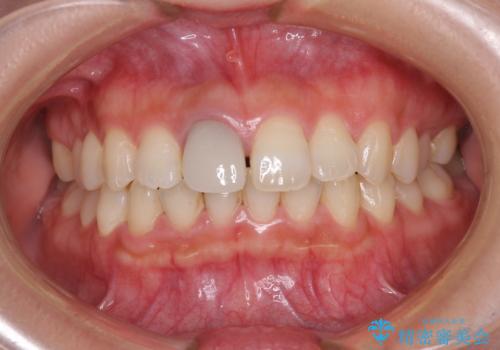

不自然なセラミッククラウンを自然なセラミックに

- 近医にて被せた前歯のクラウンの色の違いを気にして来院された患者様です。

オーダーメイドのオールセラミッククラウンにて補綴することとしました。

元々すきっ歯であったため、隙間を全て埋めると左右で大きさがアンバランスとなることが懸念されました。

違和感のない程度に隙間を小さくして、自然な見た目に仕上げました。